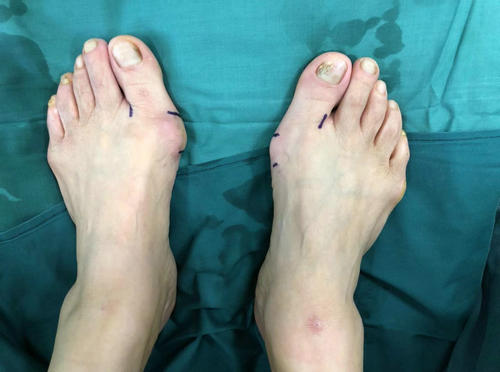

家住贾汪区的李大姐,20年前发现双足踇外翻畸形,行走时疼痛,但一直未予重视,8年前畸形加重,在徐州某家医院做了踇外翻手术,治疗后效果不好,近几个月疼痛逐渐加重。

踇外翻

术前X线

李大姐多方打听,3月11日上午,她来到必威官方首页官网betway足踝外科专家门诊,找到了业务院长石荣剑。石院长为病人做过体检和相关影像检查后,考虑患者二次手术,恐惧开大切口,决定为患者实施微创踇外翻矫正术。